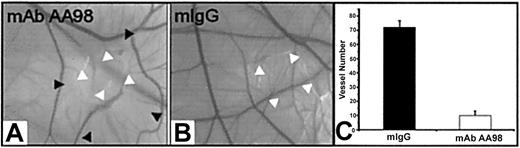

Activation, migration, and proliferation of endothelial cells play important roles in angiogenesis.1,2 We therefore investigated the effect of mAb AA98 on angiogenesis in the CAM assay. The function of CD146 in such experimental settings has not been addressed in previous studies. Placed on CAMs of day-6 embryos were 1, 5, 10, or 20 μg mAb AA98 or control mIgG absorbed on small filter disks. We used 20 embryos per group for mAb AA98 treatment and 10 embryos per group for mIgG treatment. After 12 hours of incubation, areas surrounding the applied mAb AA98 were nearly avascular. These avascular zones became larger with increasing incubation time. At 24 hours of incubation, the zone size reached about 10 mm2, and no evidence of any inflammatory reaction or hemorrhage was seen in the implant area (Figure 3A). In mAb AA98—treated CAMs, the frequency of avascular zones at the implantation sites was observed to increase with increasing amounts of antibody: 13 of 20 CAMs at 1 μg, 15 of 20 CAMs at 5 μg, 18 of 20 CAMs at 10 μg, and 20 of 20 CAMs at 20 μg. The mAb AA98—treated areas were conspicuous by the scarcity of sprouting or branching capillaries. Their blood vessel density was reduced approximately 7-fold compared with mIgG-treated CAMs (Figure 3C).

mAb AA98 inhibits angiogenesis in CAM assays. (A-B) CAM angiogenesis assays showing an almost avascular area in the CAM where the disk carrying 10 μg mAb AA98 was implanted and incubated for 24 hours (A). Normal vascularized CAMs were observed with 10 μg mIgG for 24 hours (B). White arrowheads point to implanted disk, and black arrowheads indicate the borders of the almost avascular area. (C) The number of small branching capillaries was counted within a defined area of 72 mm2surrounding the implanted disk. In each group, 10 embryos were used and the data represent the mean values (± SEM).